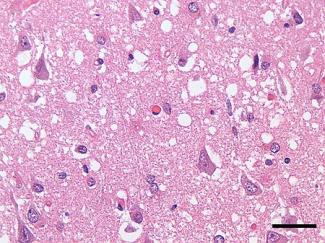

Το prion προκαλεί τρέλα καθώς εκφυλίζει τον εγκέφαλο δημιουργούνται άνοια , αστάθεια βαδίσματος και ισορροπίας ,σπασμούς , αλλαγή συμπεριφοράς η προσωπικότητας διαταραχή ομιλίας ως και απώλεια μνήμης , κατάθλιψη και παράνοια .